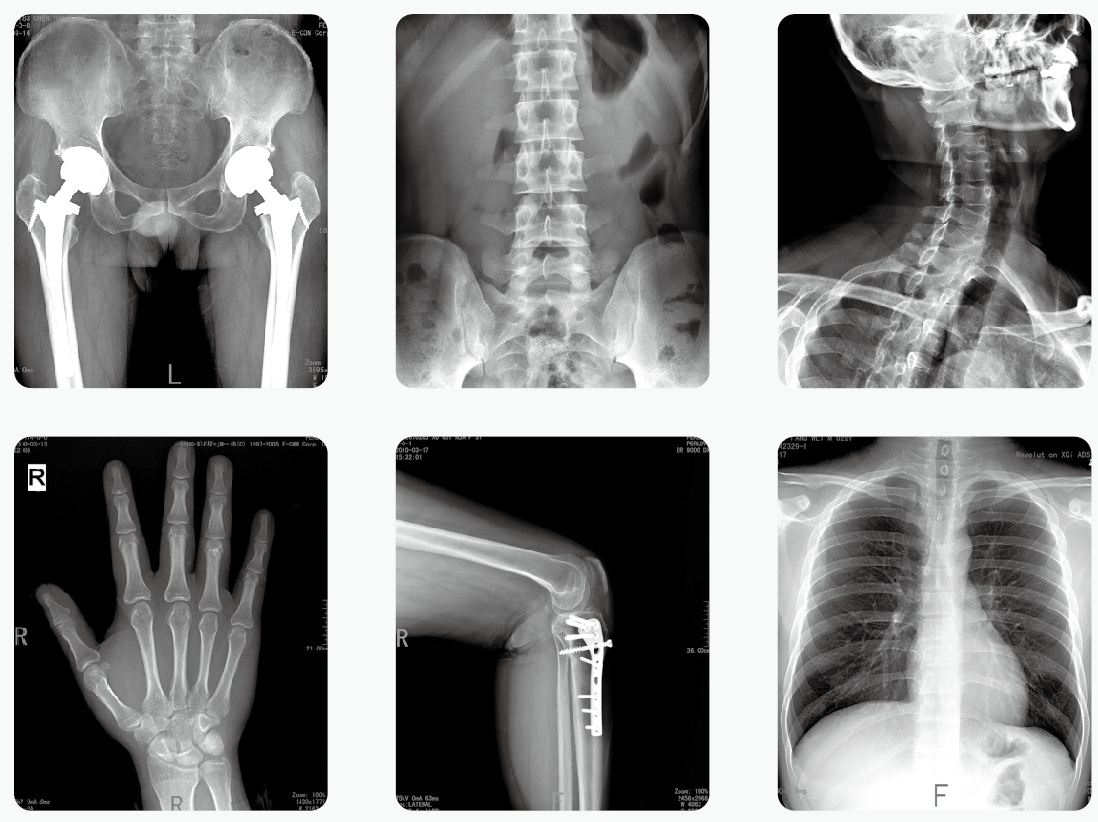

通過(guò)醫(yī)用X光機(jī)檢查,臨床醫(yī)生可以獲取病人很多重要的,甚至性命攸關(guān)的醫(yī)療信息,比如肺炎、骨折、腸梗阻等。這些普通X光檢查,對(duì)平常人而言就像是拍數(shù)碼照相,咔~可以了。但是對(duì)孕婦而言,有時(shí)的確是一個(gè)艱難的決策。那么,醫(yī)用X光機(jī)檢查,孕婦到底能不能做?

其實(shí),絕大部分醫(yī)用X光機(jī)檢查的部位都是四肢、頭、牙齒或者胸部,孕婦的生殖腺并沒(méi)有直接暴露在X光下。因此,在這些情況下,只要合理曝光及防護(hù),對(duì)胎兒是沒(méi)有危害和影響的。

但是,如果孕婦需要做腹部、盆腔、腰椎等醫(yī)用X光機(jī)檢查,此時(shí)胎兒是直接暴露在X光下的,這種情況就需要與醫(yī)生探討X光檢查的利弊后再做決定。